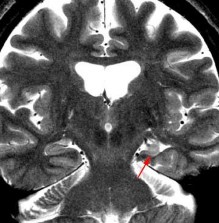

Hình 1.14. Tổn thương não do huyết khối tĩnh mạch não

(Hình ảnh do người viết cung cấp)